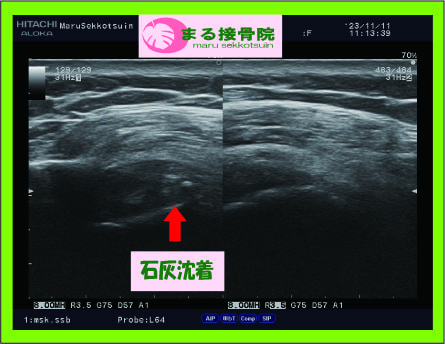

こういう、急な肩の痛みの場合、臨床的にとても多いのが、「石灰沈着性腱板炎」というものがあります。

石灰沈着性腱板炎.jpg

では、石灰沈着性腱板炎とはどのようなものでしょうか??

肩の筋肉内に沈着したリン酸カルシウム結晶(石灰)によって、原因不明で突然、炎症が生じて肩の痛みで動かせる範囲が狭くなる状態です。